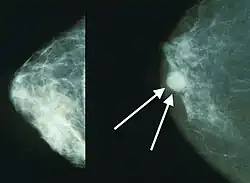

Breast cancer screening refers to testing otherwise-healthy women for breast cancer in an attempt to diagnose breast tumors early when treatments are more successful. The most common screening test for breast cancer is low-dose X-ray imaging of the breast, called mammography.[28] Each breast is pressed between two plates and imaged. Tumors can appear unusually dense within the breast, distort the shape of surrounding tissue, or cause small dense flecks called microcalcifications.[29] Radiologists generally report mammogram results on a standardized scale – the six-point Breast Imaging-Reporting and Data System (BI-RADS) is the most common globally – where a higher number corresponds to a greater risk of a cancerous tumor.[30][31]

A mammogram also reveals breast density; dense breast tissue appears opaque on a mammogram and can obscure tumors.[32][33] BI-RADS categorizes breast density into four categories. Mammography can detect around 90% of breast tumors in the least dense breasts (called "fatty" breasts), but just 60% in the most dense breasts (called "extremely dense").[34] Women with particularly dense breasts can instead be screened by ultrasound, magnetic resonance imaging (MRI), or tomosynthesis, all of which more sensitively detect breast tumors.[35]

Still, mammography has its disadvantages. Overall, screening mammograms miss about 1 in 8 breast cancers, they can also give false-positive results, causing extra anxiety and making patients overgo unnecessary additional exams, such as bioposies.[41]